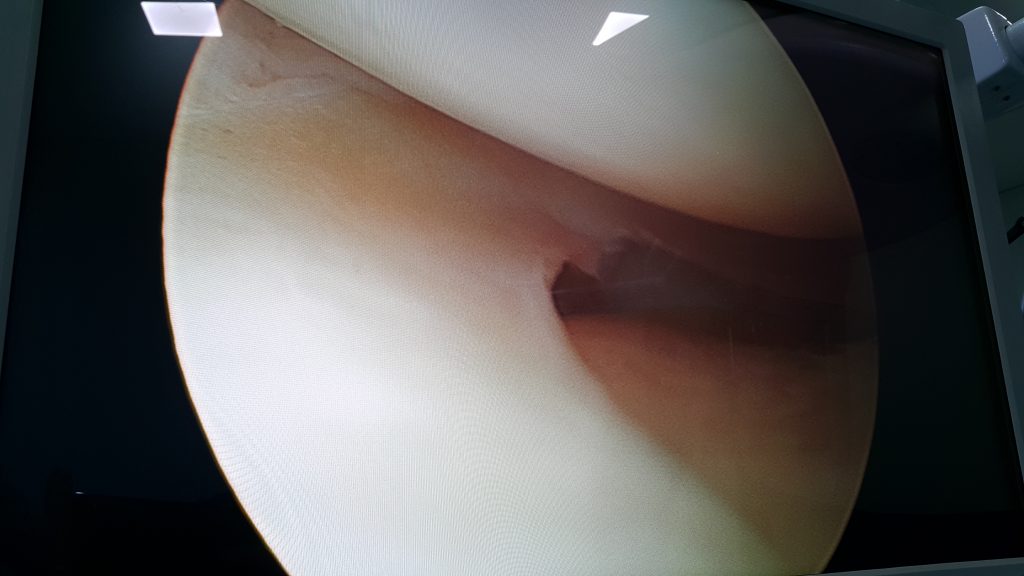

Osteotomia de Realinhamento do Fêmur – Imagens

Osteotomia de Realinhamento do Fêmur

Imagens

Lesões dos Meniscos